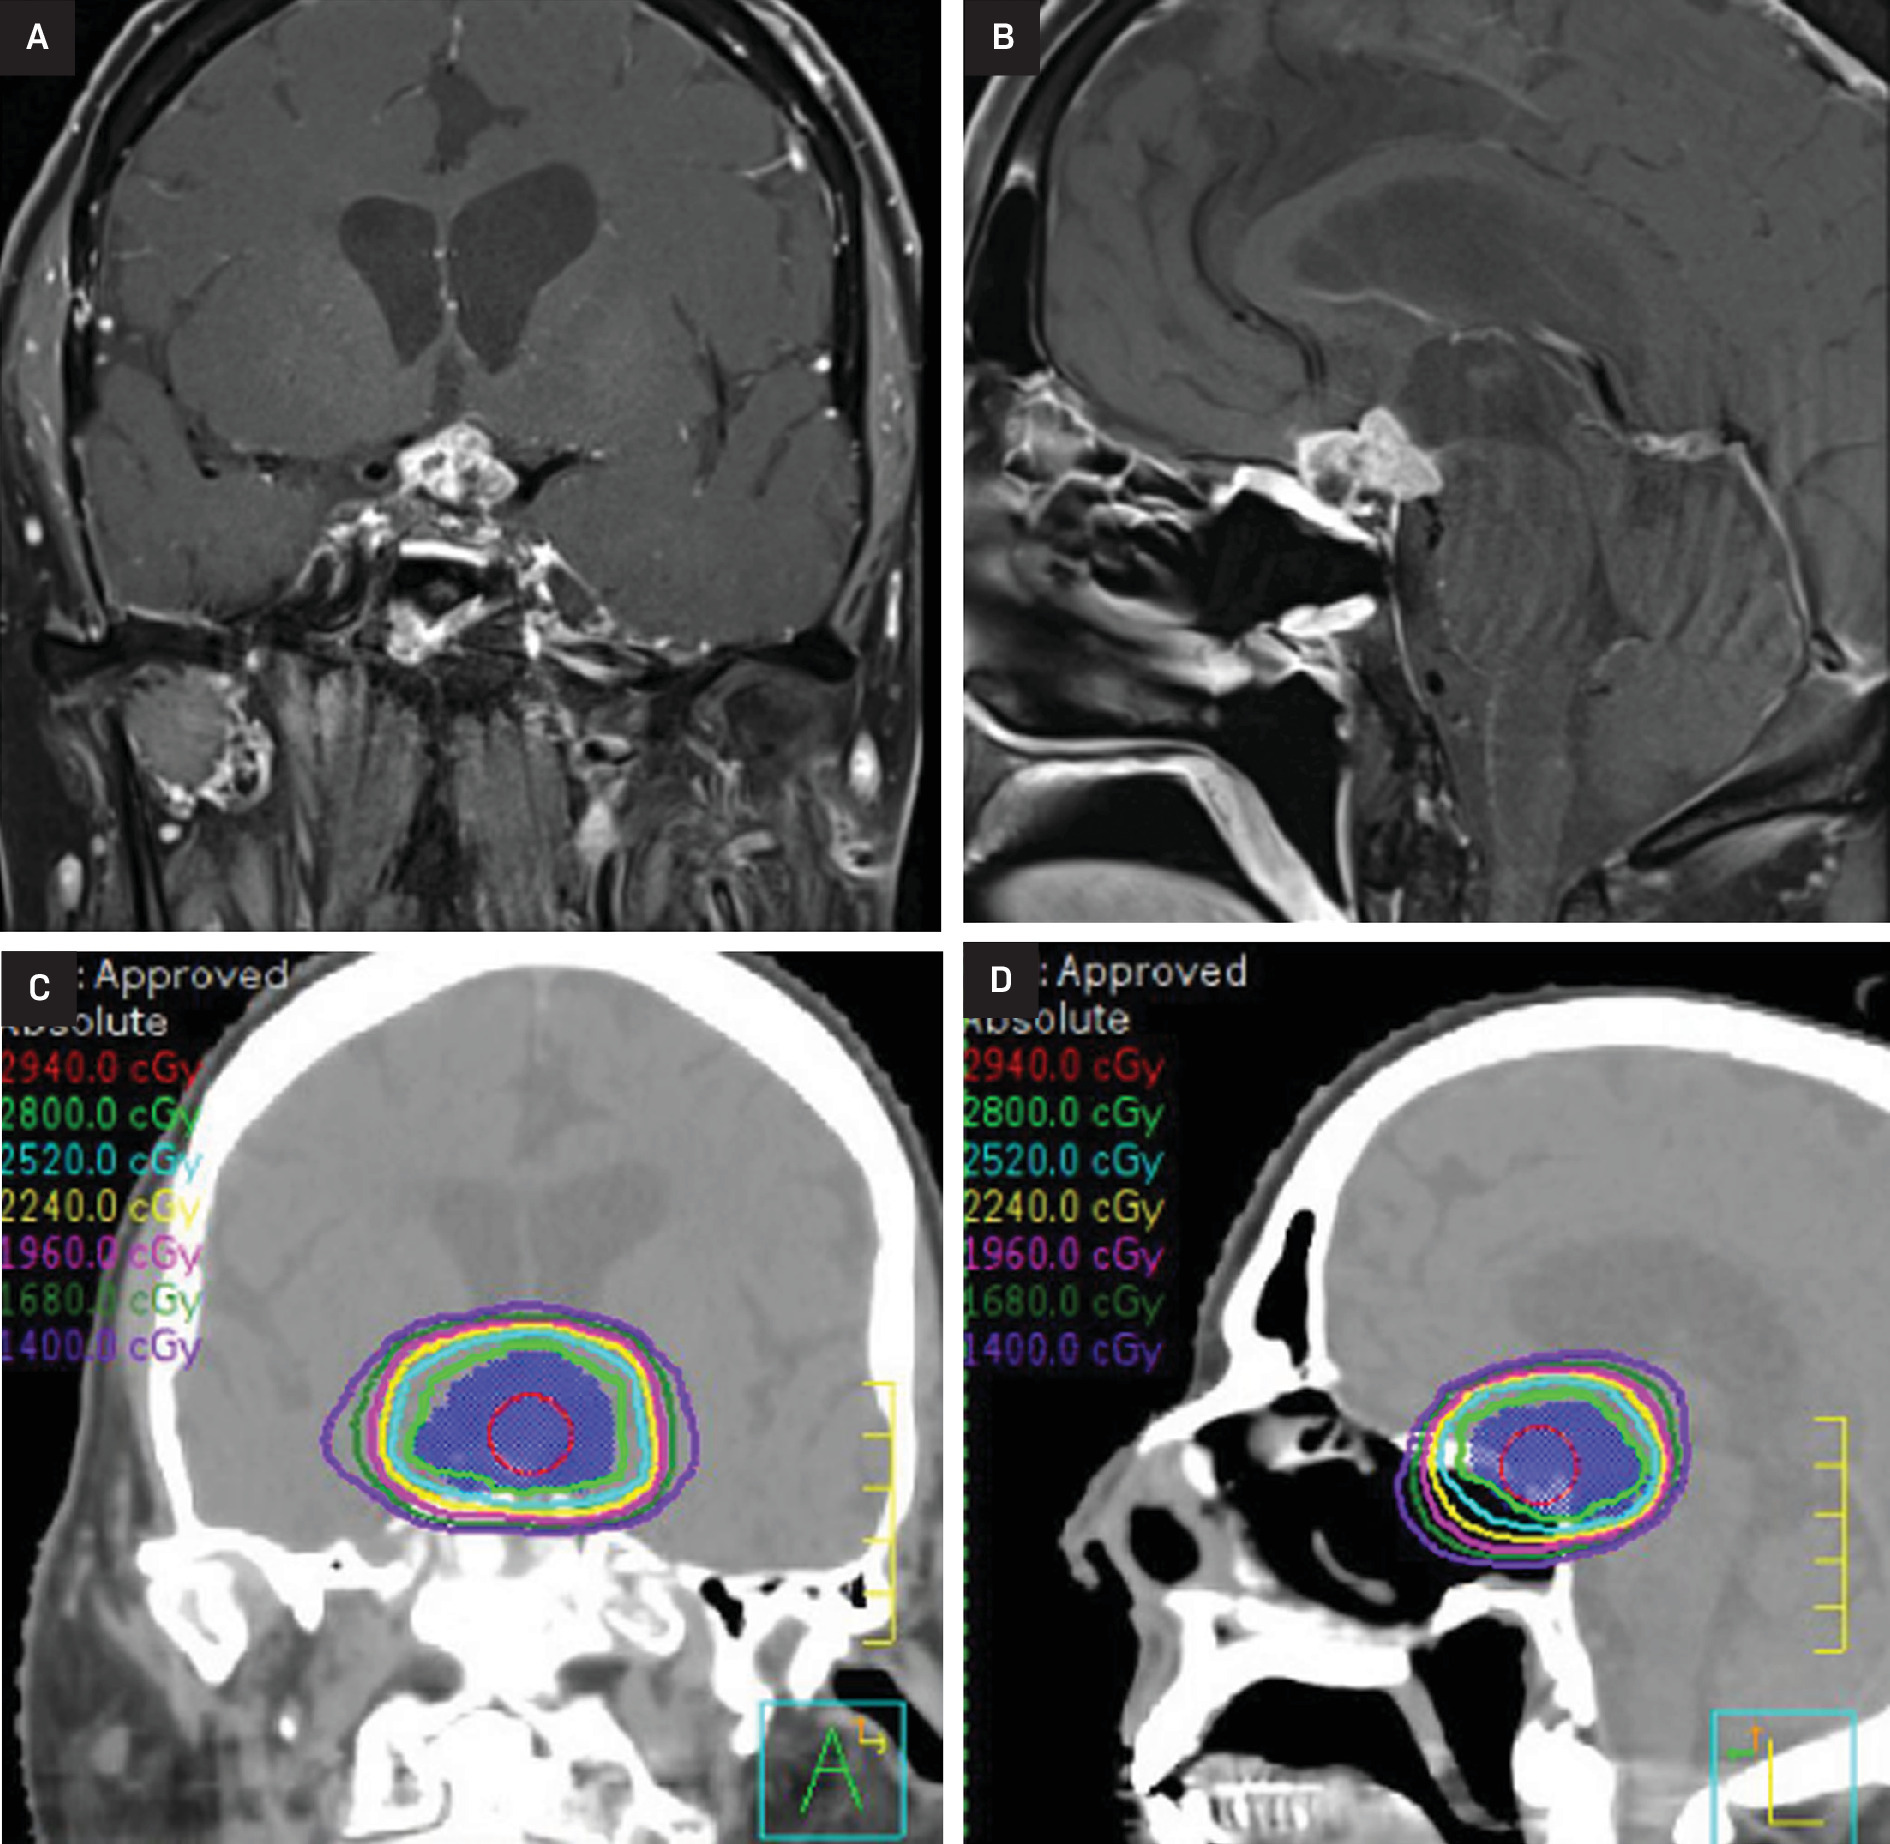

At this time, after a multidisciplinary discussion, the patient was referred to radiation oncology for consideration of additional RT. Ultimately, he was treated to a dose of 28 Gy in 14 fractions using 6 MV photons with 2 non-coplanar VMAT arcs (Figure 2). He again experienced no immediate side effects except for significant fatigue. MRI scans at 3 and 6 months post re-RT demonstrated a decrease in size and enhancement of the suprasellar abnormality with stable vision (Figure 3).